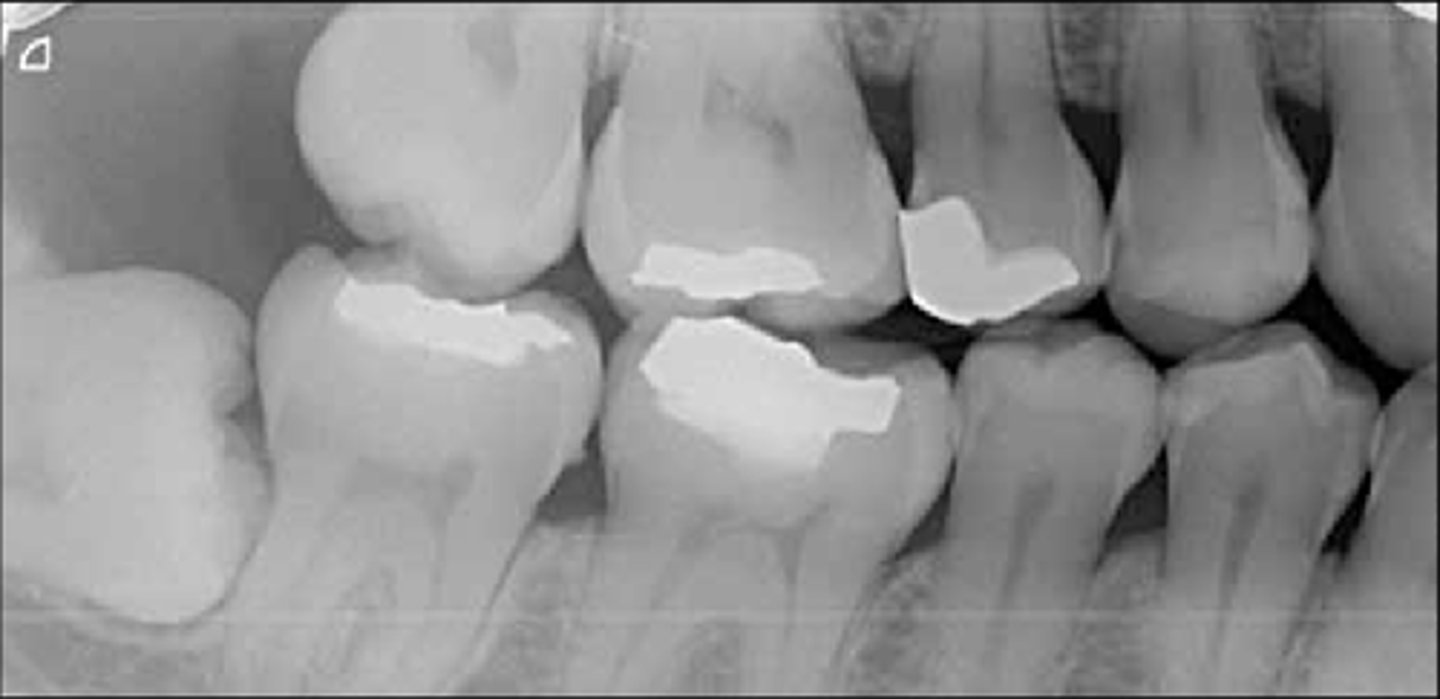

composite restorations radiographically

amalgam restorations look like radiographically

overhang